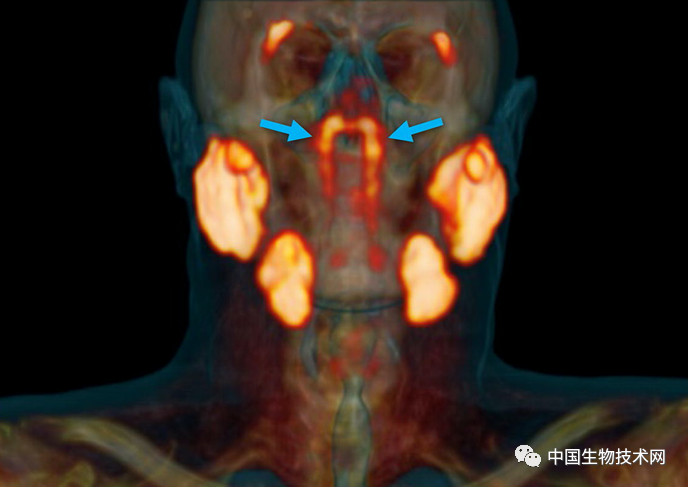

“管状腺”结构,用蓝色箭头表示,其他主要唾液腺用橙色表示。图片来源:荷兰癌症研究所

该研究通讯作者、荷兰癌症研究所的放射肿瘤学家Wouter Vogel解释说:“人有三大唾液腺(腮腺、下颌下腺和舌下腺),但新发现的不是在那里。据我们所知,鼻咽中仅有的唾液腺或粘液腺在显微镜下很小,多达1000个腺体均匀分布在整个粘膜上。所以,想象一下,当我们发现这些时有多惊讶吧。”

Vogel团队新发现的要大得多,它显示出似乎是先前被忽视的一对腺体,表面上看是第四大主要唾液腺,位于鼻咽后部、上颚上方,靠近人类头部的中心。

该研究第一作者,阿姆斯特丹大学的口腔外科医生Matthijs Valstar说:“这两个新发现的区域也具有唾液腺的其他特征。根据它们的解剖位置(在咽鼓管上方),我们称之为‘管状腺’(tubarial glands)。”

在对所有100例患者进行的PSMA PET/CT扫描,均发现存在这些管腺,并且对两名尸体(一男一女)的身体检查也显示出神秘的双侧结构,从宏观上可见引流管开口朝向鼻咽壁。